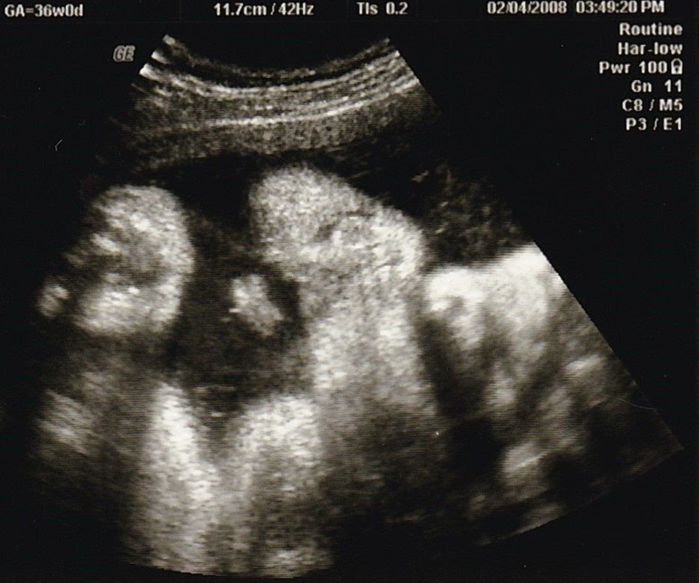

妊娠36週目のエコー写真

産院では、輸血が必要になったときのために、希望者は事前に自己採血し、院内保管してくれるということで、私は念のため希望しました。「たまごクラブ」や産院でもらった資料にある「入院準備のリスト」を見ながらチェックしました。